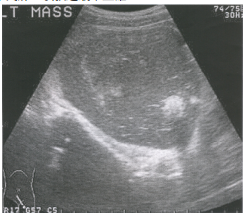

71 一位 21 歲女性病患所做骨盆腔影像檢查如圖所示,下列那一項敘述最不正確?

(A)為達到正確診斷,需進一步做經陰道之超音波掃描 (B)檢查時有賴於介質 (C)最可能的影像診斷為源自卵巢之囊性畸胎瘤 (D)其音波頻率大多介於 2.5 MHz 至 10 MHz 之間